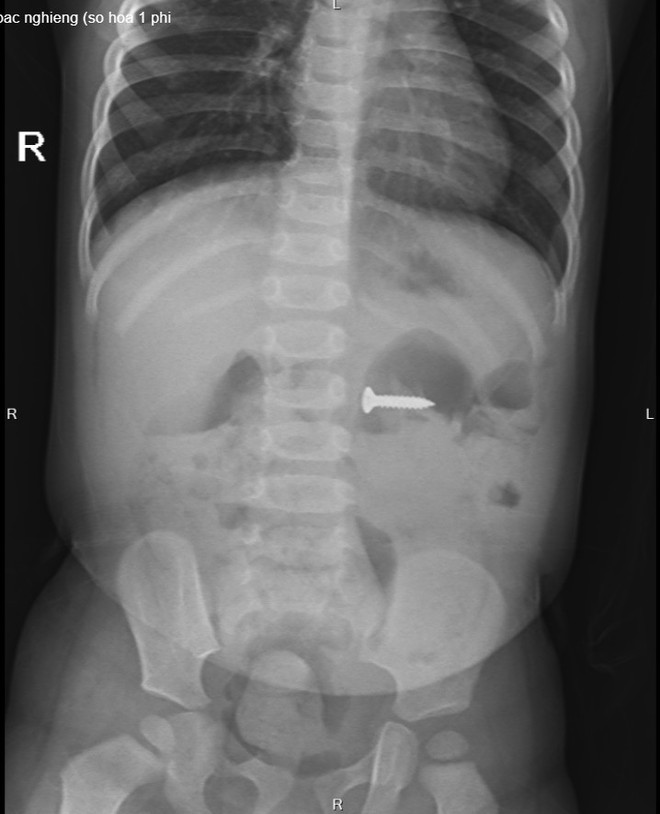

Tại Bệnh viện Sản Nhi tỉnh Phú Thọ, các bác sỹ chỉ định cho bé chụp X-quang thăm dò và phát hiện dị vật đinh vít sắc nhọn kích thước 2cm trong dạ dày, vị trí ngang đốt sống D3 của trẻ. Sau khi hội chẩn với các bác sỹ khoa Ngoại nhi tổng hợp và giải thích với gia đình, bệnh nhi được chỉ định gây mê nội soi tiêu hóa cấp cứu gắp dị vật.

Sau 5 phút, các bác sỹ Khoa Chẩn đoán hình ảnh-thăm dò chức năng gắp ra được dị vật là 1 chiếc đinh ốc vít có một đầu sắc nhọn nằm trong dạ dày của bệnh nhi. Các bác sỹ đánh giá, với tính chất sắc nhọn của đầu đinh, nếu không loại bỏ kịp thời có thể gây tổn thương đâm thủng thành ruột, dạ dày, thậm chí có thể gây tổn thương nhiều vị trí mà chiếc đinh đi qua.

Chiếc đinh vít sắc nhọn nằm trong dạ dày bệnh nhi trên phim chụp X-quang. (Ảnh: BVCC)